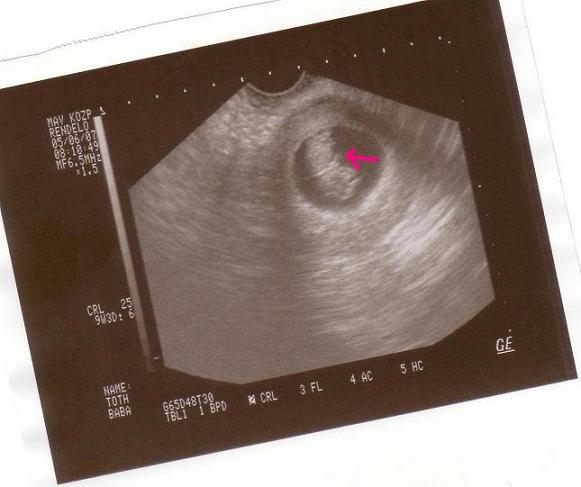

na és a képecske

na és a képecske